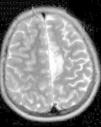

Ingresa en nuestro centro a los 7 años de edad, por presentar varias crisis tónico-clónicas que afectan principalmente al hemicuerpo derecho, con pérdida de fuerza posterior a este nivel. En el TC craneal al ingreso se observaron lesiones hipodensas a nivel parafalcial anterior izquierdo y fronto-parietal izquierdo y en la RM cerebral lesiones córtico-subcorticales a nivel frontal superior, frontal medio y parietal, de aspecto tumefactivo y atrofia marcada del hemisferio cerebral izquierdo (figs. 1 y 2). No se apreciaron alteraciones en el árbol vascular. En el EEG presentaba asimetría interhemisférica con gran lentificación en el hemisferio izquierdo y actividad paroxística focal con ondas agudas, puntas y complejos punta-onda de elevado voltaje, principalmente a niveles frontal y fronto-temporal izquierdos. La ecografía Doppler de troncos supraórticos no mostró alteraciones. Se solicitaron estudios de laboratorio, incluyendo estudio metabólico completo y serologías virales, todos ellos anodinos. La citoquímica de líquido cefalorraquídeo (LCR) fue normal y las PCR de virus neurotropos en LCR negativas. Tampoco se apreciaron células malignas. Otros estudios de inmunología realizados comprenden anticuerpos onconeuronales, negativos; ANA 1/80 patrón moteado, y anti-RNP-A positivo. Como pruebas de segundo nivel solicitamos RM cerebral con espectroscopia que mostró varias lesiones córtico-subcorticales, alteraciones en el cociente N-acetilaspartato/colina e inversión en el cociente de lípidos/lactato, sin demostrarse aumento de lactato en el LCR. Otros estudios llevados a cabo: fondo de ojo, estudio cardiológico, audición, biopsia de piel y de músculo, resultaron normales. Los potenciales evocados visuales no resultaron alterados y en los potenciales evocados somatosensoriales se encontraron anomalías en la vía somatosensorial procedente de ambas extremidades superiores, con respuesta cortical de amplitud reducida bilateralmente. Bajo la sospecha de síndrome de Rasmussen se envía a hospital de referencia, donde realizaron nueva RM cerebral (secuencias DWI, T1, DP-T2, FLAIR, T1D3) con aumento de surcos corticales y pérdida de volumen del hemisferio cerebral izquierdo, compatible con esta enfermedad.